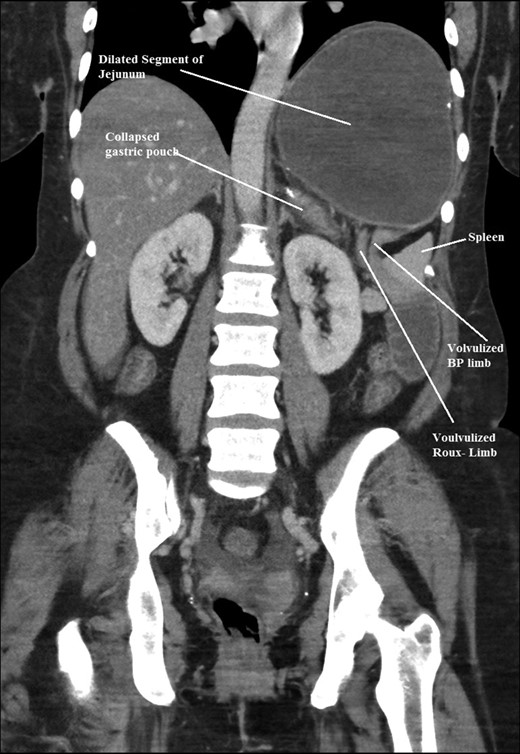

The intraoperative findings were not consistent with the radiological findings (Figs 1–4). As shown in the CT scan of abdomen and pelvis; multiple loops of dilated small bowel were seen, more predominantly dilated and matted bowel complex just above the spleen. The dilated bowel complex was decompressed using needle aspiration to help reduction of the bowel loops. The ileo cecal junction was then identified and traced back to the perisplenic hilar region. The trifurcation of three bowel loops (Roux limb, biliopancreatic limb and common limb) were identified with identification of ligament of Treitz. The prior gastric bypass was of ante colic- ante gastric type and Peterson’s defect was not closed. The above described bowel trifurcation had sunken postero- inferior to the spleen and had herniated through a potential space underneath the spleen and torsed around the splenic vessels and hilum. This picture was consistent with perisplenic small bowel volvulus. As noted earlier there was a massively dilated proximal small bowel segment above the spleen, displacing it caudally. Careful adhesiolysis was performed inferior to the spleen to release the segment of the trifurcation. The bowel segments once reduced were assessed and appeared viable. Of note, the spleen appeared better perfused after reduction. The remnant hernia defect of size 2 × 3 × 2.5 cm around the hilar region was then approximated using interrupted non-absorbable sutures. Enterotomy at the decompression site was closed with non absorbable suture. All potential sites of IH were re-examined and there was no evidence of any other internal herniation. Coelomic cavity was thoroughly irrigated and operation concluded successfully. Postoperative hospital stay was uneventful, and the patient was discharged home after two days.

Coronal CT scan of abdomen and pelvis showing Dilated jejunal segment causing caudad splenic displacement.